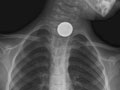

- Encontrar objetos extraños, como monedas u otros trozos pequeños de metal, en el conducto que va al estómago (esófago), las vías respiratorias o los pulmones. Es posible que en una radiografía de pecho no puedan observarse alimentos, nueces ni fibras de madera. Vea una radiografía de una moneda en el esófago.

Se observa un objeto extraño en el esófago, en las vías respiratorias o en los pulmones. |